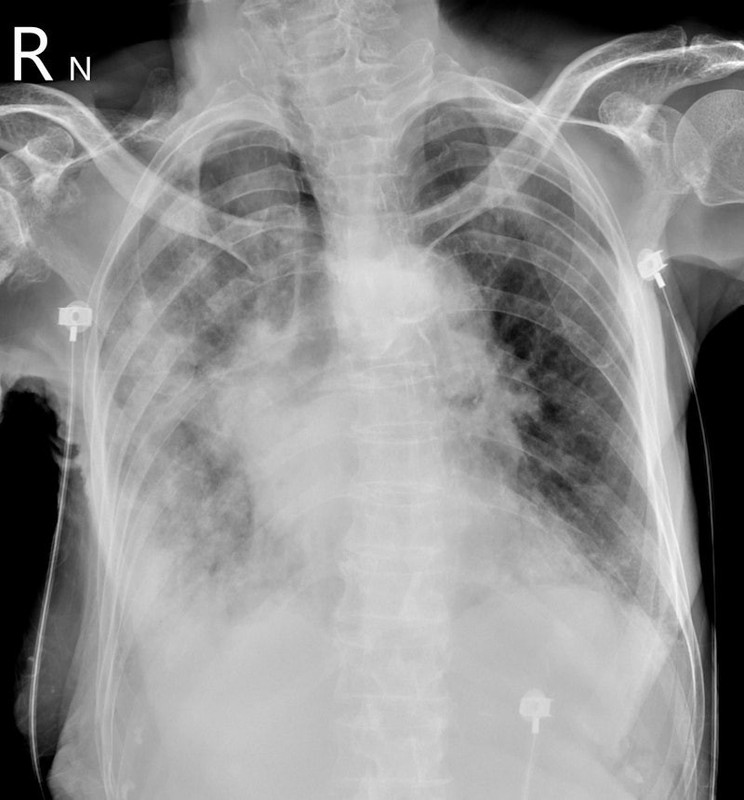

Bên cạnh đó, nhiều thông tin cho biết, khi tình trạng của Từ Hy Viên trở nặng, kết quả chụp CT cho thấy cả hai lá phổi của Từ Hy Viên đã trắng xóa. Không lâu sau, cô trút hơi thở cuối cùng.

Ngày 5/2, bác sĩ Tô Nhất Phong, chuyên khoa lồng ngực tại chi nhánh Dương Minh của Bệnh viện Thống nhất thành phố Đài Bắc (Đài Loan, Trung Quốc), giải thích rõ hơn về tình trạng "lá phổi trắng" của nữ diễn viên xấu số. Theo bác sĩ này, "phổi trắng xóa" thực chất phản ánh tình trạng viêm phổi nặng dẫn đến khó thở.

Khi viêm phổi nặng xảy ra, phế nang sẽ chứa đầy đờm và nước bị viêm. Khi phế nang phủ đầy đờm và nước, không khí không thể vào. Do đó, theo bác sĩ họ Tô, phổi trắng thực chất là "bệnh nhân bị chính đờm của mình nhấn chìm".

Hình ảnh phổi trắng xóa của một bệnh nhân từng được bác sĩ Tô Nhất Phong chia sẻ. Nguồn: BSCC

Bác sĩ Tô nói thêm, khi phổi trắng xuất hiện, bệnh nhân thở mạnh nhưng phổi mất khả năng trao đổi khí, oxy trong máu tiếp tục giảm. Khi độ bão hòa oxy trong máu giảm xuống dưới 89%, đó là tình trạng thiếu oxy. Nếu không được điều trị, bệnh nhân có thể tử vong trong vòng nửa ngày hoặc vài giờ do ngừng tim và ngừng hô hấp.